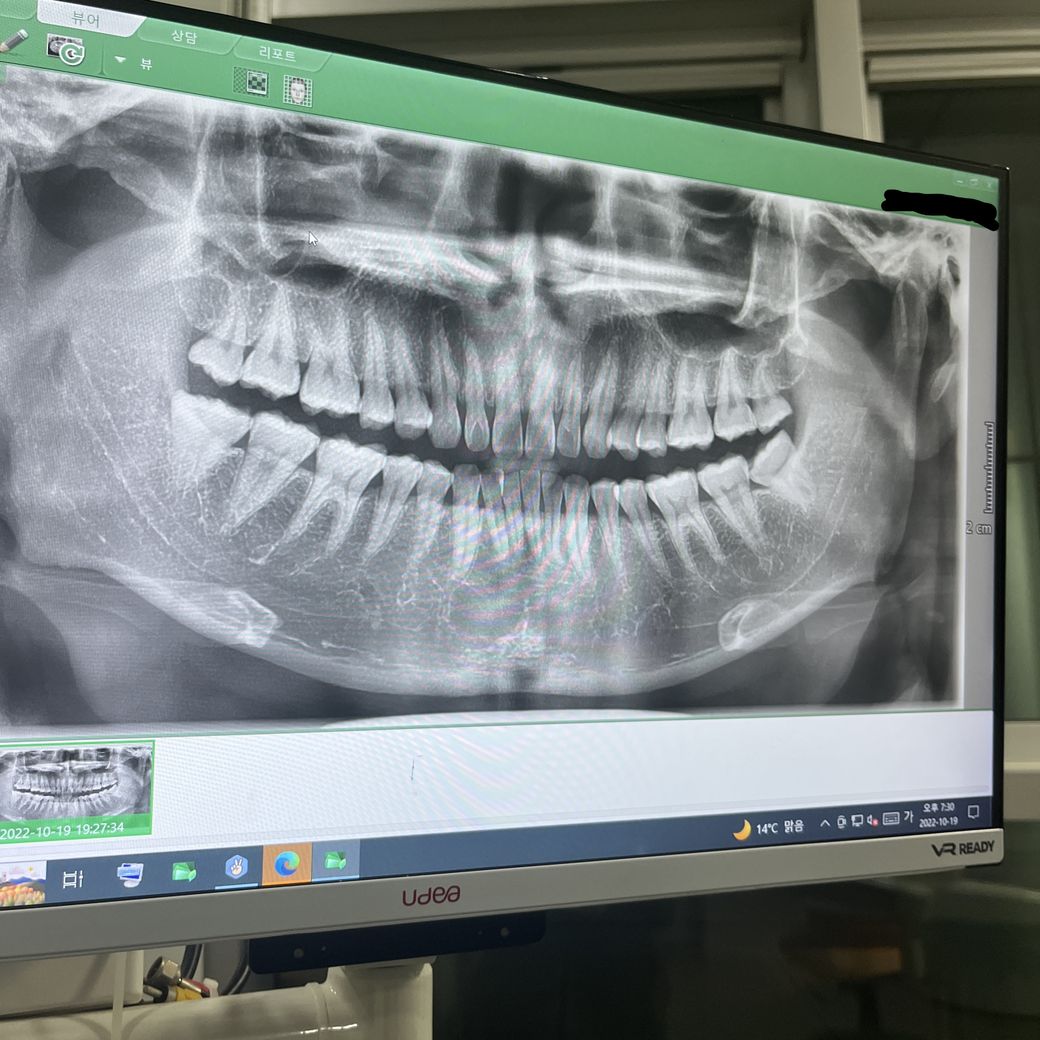

사랑니 4개 전부 다 자란 상태인데 이게 매복인가요..?

사링니 4개가 전부 다 자란 상태인데 잇몸이 조금 부어서 뽑았는데 사랑니 4개가 전부 매복인가요?

치과에서 상세진단서를 받앗는데 단순매복1개 복잡매복2개 완전매복1개로 진료 받아서 궁금해서 물어보니 맞다고만하고 이유를 얘기안해줘서 여기에서라도 도움을 받고 싶어 올립니다ㅠ.ㅠ

엑스레이 사진상으로 보면 사랑니가 4개가 잇으신거 같네요. 일단은 4개다 사진상으로는 단순매복으로 보이지만, 실제로보면 다를수 있습니다. 제 개인적인 판단으로는 상악은 단순매복 하악은 단순 매복 or 복잡 매복일 가능성이 있네요.완전매복은 아니실꺼 같습니다.

• 안녕하세요. 정진석 치과의사입니다.

해당 사진으로 보아서는 매복되었다는 것은 환자 분 기준으로 왼쪽 아래에 있는 치아를 제외하고는 모두 완전 매복되지는 않았습니다. 부분 매복되어 있습니다. 다만 복잡, 단순, 완전을 구분하는 기준은 단순히 파노라마가 아니라 PA라고 해서 치근단 사진을 찍어서 판단하게 됩니다. 따라서 지금 말씀드리는 것은 정확하지 않습니다.

치아가 잇몸위로 완전히 뚫고 나와있는 경우가 아니라면 부분 매복 등의 용어를 사용합니다.

사랑니의 매복은 잇몸이 사랑니를 얼마나 덮고 있는지를 확인해야 합니다.

사진상으로는 잇몸뼈 밖으로 맹출되어 있지만 연조직의 정확한 위치를 알기 힘들기 때문에 매복이 있다면 잇몸이 치아를 덮고 있을수 있어요.